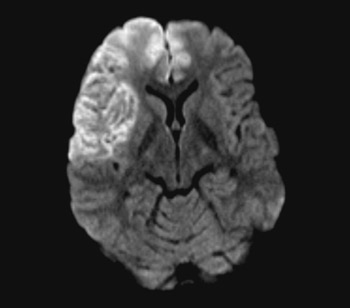

Figure 1

A person in his 20s with known migraine with aura developed infarcts in the right middle cerebral artery and both anterior fields of supply (Figure 1 shows a magnetic tomography diffusion weighted series). Cerebral computed and magnetic tomography with magnetic resonance angiography (MRA) after admission showed normal blood flow and no sign of dissection or vasculitis. Hemicraniectomy became necessary after development of malignant cerebral oedema. MR angiography the first postoperative day showed open arteries (Figure 2 shows an open carotid top (white arrow), normal basilar top (red arrow), and a non-closed circle of Willis, an anatomically normal variant (stars). Testing for illegal drug use, anticardiolipins, anti-nuclear antibodies, neurone antibodies and tumour markers was negative. Transoesophageal echocardiography showed a minimally patent foramen ovale, according to a cardiologic evaluation unlikely to be related to the episode. The patient developed severe brain stem involvement and MR angiography showed narrowing of the posterior branch of the basilar artery (arrows in Figure 3). Arterial vessel spasms were suspected retrospectively. The first suspected vessel spasm, in the right – middle/anterior branch, remained undocumented. The second, in the posterior branch of the basilar artery, was documented postoperatively (arrows in Figure 3). Images of several newly developed infarcts in the posterior circulation are not shown. Three weeks after the hemicraniectomy the angiogram was normalised (Figure 4).